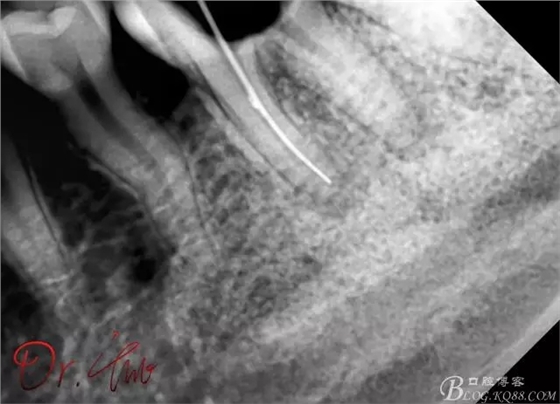

試主尖,近中頰側(cè)試主尖,此時手用銼02錐度的已擴到30號,可以明顯感覺到臺階位置,挫預(yù)彎后找好正確位置可順利到達根尖,但是機用銼就是下不去,也是郁悶

試主尖,在30號02錐度K挫到達根尖后,用02錐度牙膠尖找準位置,進行試尖

最后根充,明顯可看到臺階位置,期待預(yù)后效果